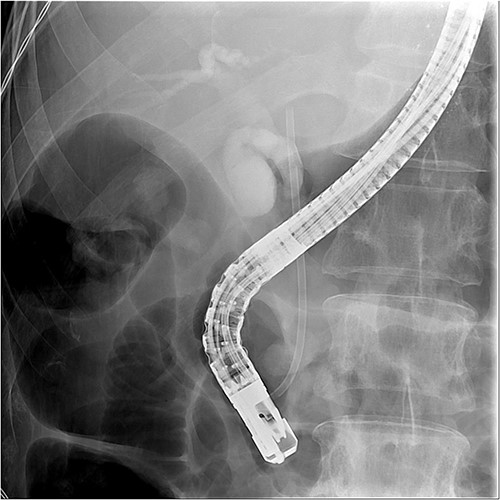

Initial laboratory findings revealed significant hyperbilirubinemia, liver enzyme elevation and mild PT prolongation. Abdominal computed tomography showed a CBD stone caused obstruction, resulting in upstream biliary dilatation and acute cholecystitis (Fig. 1). Besides, small caliber of inferior vena cava, splenic vein, and right iliac veins with thrombosis and prominent collaterals formation was also shown on the image.

Abdominal CT revealed CBD stone resulting in upstream biliary dilatation and acute cholecystitis.